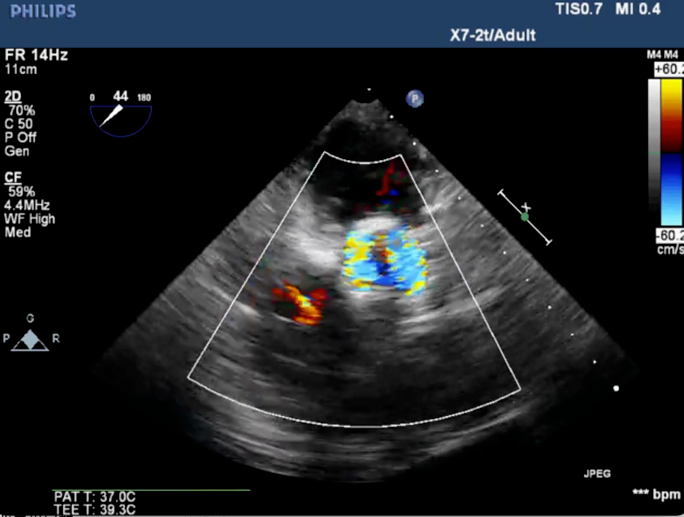

心脏超声诊断:主动脉瓣明显增厚钙化伴极重度狭窄及轻度反流(最大流速: 6.07 m/s,峰值压差:147 mmHg,平均压差:65 mmHg),左室壁明显增厚致乳头肌水平以上至心尖部梗阻(峰值压差123 mmHg),轻度二尖瓣狭窄

术后心电监护未见传导阻滞,心超提示人工主动脉瓣工作良好,瓣叶启闭正常,主动脉瓣峰值流速2 m/s,平均跨瓣压差6 mmHg,轻度瓣周漏。